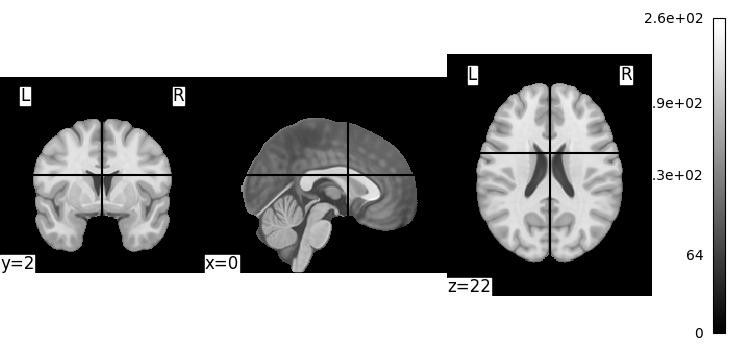

Let’s quickly plot this file:

from nilearn import plotting

plotting.plot_img(MNI152_FILE_PATH)

<nilearn.plotting.displays._slicers.OrthoSlicer object at 0x7587ebf68e50>

This is not a very pretty plot. We just used the simplest possible code. There is a whole section of the documentation on making prettier code.